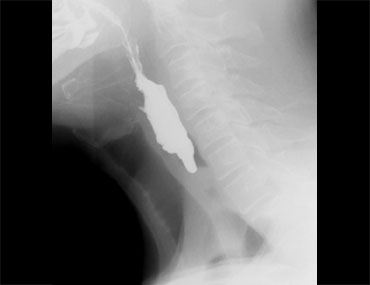

Các hình ảnh là của một bệnh nhân có cảm giác vướng họng (globus sensation).

Nguyên nhân là do trào ngược nặng và tình trạng tăng trương lực cơ nhẫn hầu thứ phát.

Thoát vị cạnh thực quản lớn kèm trào ngược là nguyên nhân gây ra các triệu chứng.